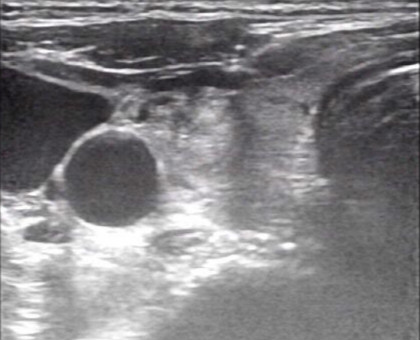

超声引导下的甲状腺结节细针穿刺活检术(US-FNAB)是指在高频超声引导下,应用无菌穿刺针(通常22-25G的甲穿专用针)穿刺甲状腺结节可疑部位,抽取部分结节成分送细胞学病理检测的一种鉴别甲状腺良恶性的方法。甲状腺结节是临床上最常见的甲状腺病变。超声在甲状腺结节评估中具有很高的敏感性及特异性,然其仅能对甲状腺结节的实现初步评估,无法给予明确的定性诊断。目前超声引导下细针穿刺活检已成为甲状腺结节评估的金标准。一方面提供甲状腺结节的重要信息如回声情况、边界、形状,有无钙化、血流情况等。另外一方面赋予细针穿刺活检精确定位的优势,极大降低了假阴性穿刺及取样的不满意情况。

超声引导下细针穿刺活检应用于临床以来,由于其对可疑甲状腺结节特异筛选及对穿刺靶向定位作用,对绝大多数结节均能实现术前评估,从而减少良性结节患者的不必要手术;并能检出恶性结节患者,使其得以及时治疗,减轻了患者病痛,节约了医疗资源。具有安全可靠、创伤小、 并发症少、取材方便、无针道转移等优点,是目前国内外各大甲状腺结节指南所推荐的、用于鉴别甲状腺结节性质的首选诊断方法。